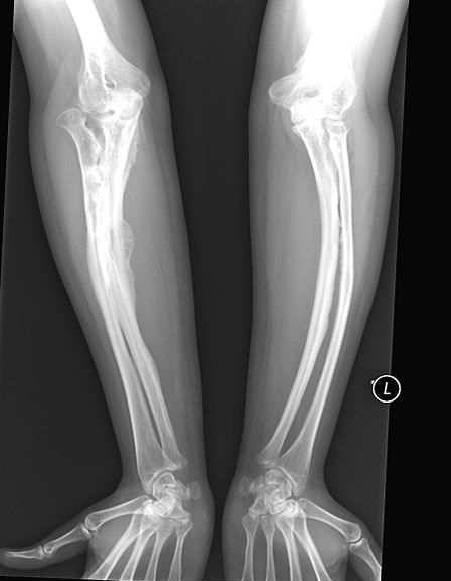

Nainen, jolla on lisääntynyt luiden hauraus, onnistui menemään onnellisena ulos naimisiin. Anastasia Marukova, joka diagnosoitiin lapsena “epätäydellinen osteogeneesi” selvisi paljon vaivaa. Hän on mursi luita 40 kertaa. Isä ei kestänyt elämää vakavaan sairauteen tytär ja jätti heidät varhain äitinsä luo. Mutta sitten Anastasia oli onnekas kanssa aviomies – rakkaansa saattaja häntä kaikkialla, koska huolimaton liike lupaa hänelle uuden käännekohdan.